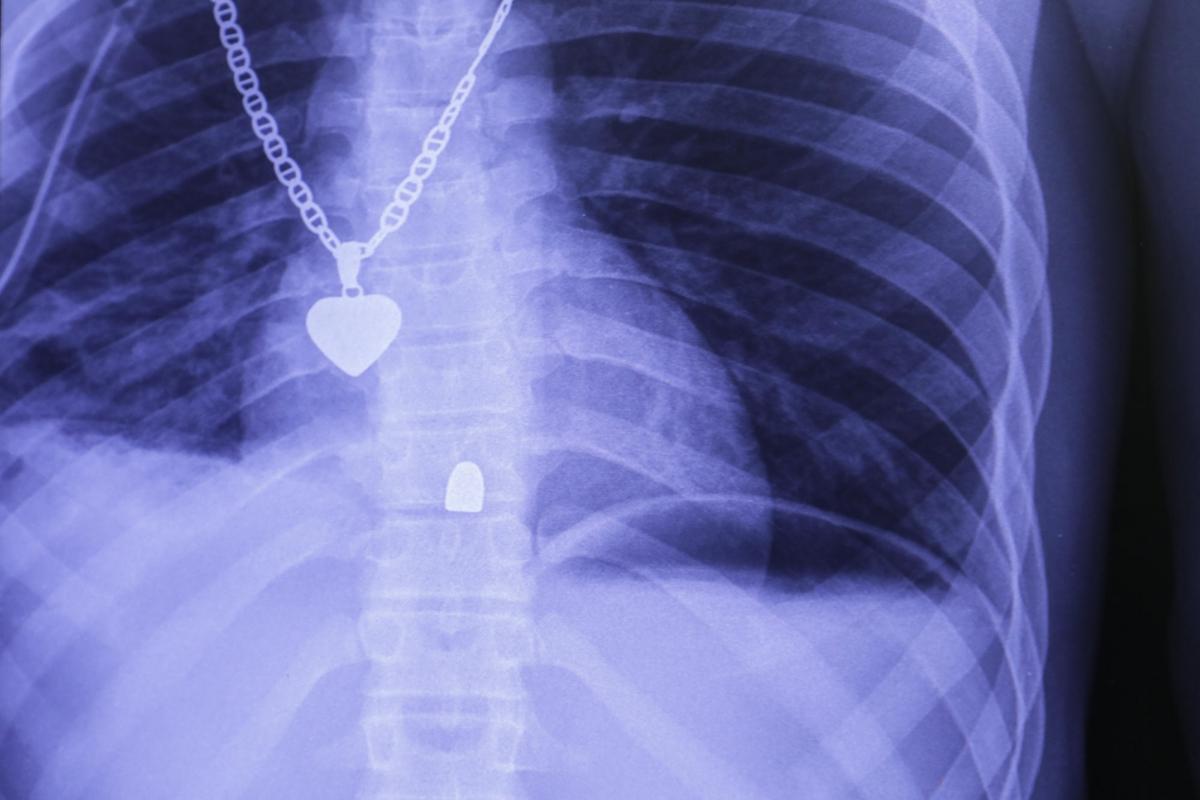

L'opération chirurgicale a permis de constater l'absence d'atteinte des organes vitaux - la balle est passée à quelques centimètres du foie. La radiographie a quant à elle confirmé les premières hypothèses posées au service des urgences : la balle n'est pas ressortie et elle s'est logée dans la colonne vertébrale du patient.

Radiographie du thorax d'un patient victime d'un tir de pistolet. La balle s'est logée dans la colonne vertébrale. L'opération qu'il a subie a permise de vérifier l'absence de lésions des organes internes.

Radiographie du thorax d'un patient victime d'un tir de pistolet. La balle s'est logée dans la colonne vertébrale. L'opération qu'il a subie a permise de vérifier l'absence de lésions des organes internes. © Nicolas Guyonnet/MSF